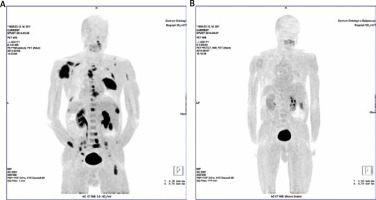

Fig. 3

Patient no. 21. Myeloma-related lesions before and after the treatment. MIP images of the FET uptake in the patient body. A) Multiple FET lesions localised in the skeleton of the pathological uptake of FET. B) MIP image after chemotherapy. Complete disappearance of pathological FET uptake may suggest metabolic response to the treatment